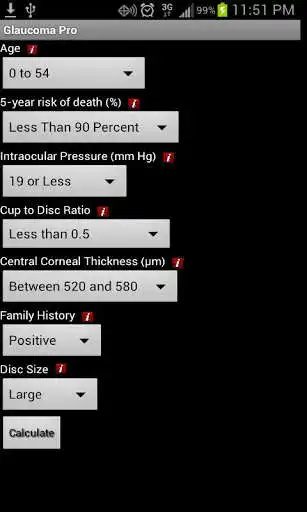

This app is based upon the journal article titled "For which glaucoma suspects is it appropriate to initiate

treatment?", published in the journal Ophthalmology. It allows the user to calculate, based upon 7 clinical criteria, whether or not treatment is indicated for a patient.